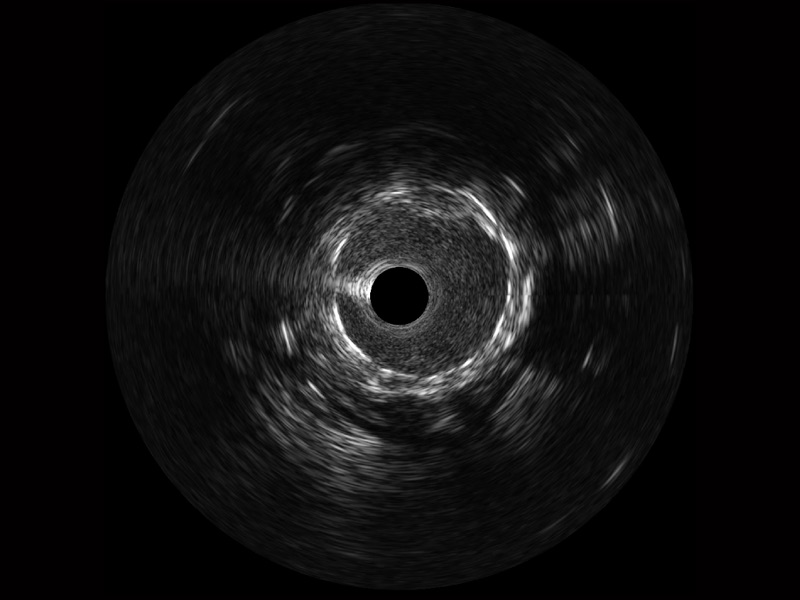

新葡的京集团8814检测站宽频IVUS图像

对比传统IVUS导管成像,新葡的京集团8814检测站宽频IVUS图像的近场支架梁显影更细腻,远场中膜外血管仍清晰可辨,兼顾远中近,兼顾分辨力与穿透深度